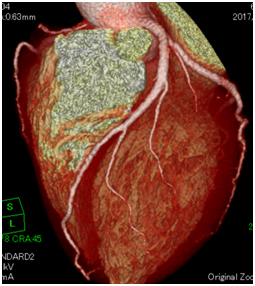

負荷心筋シンチ画像 心臓CT画像(赤丸部分 狭さく)

心臓CTボリュームレンダリング画像